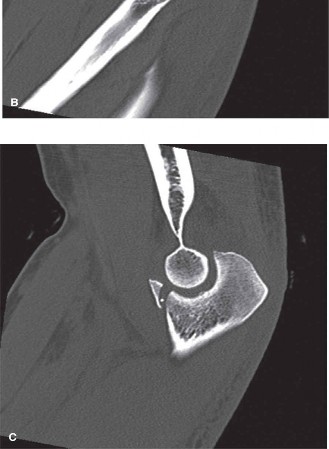

The ED physician calls you back after plain radiographs and a subsequent CT of the elbow showing fractures of the coronoid and the radial head (Fig. 6–19A–C).

Figure 6–19 A–C